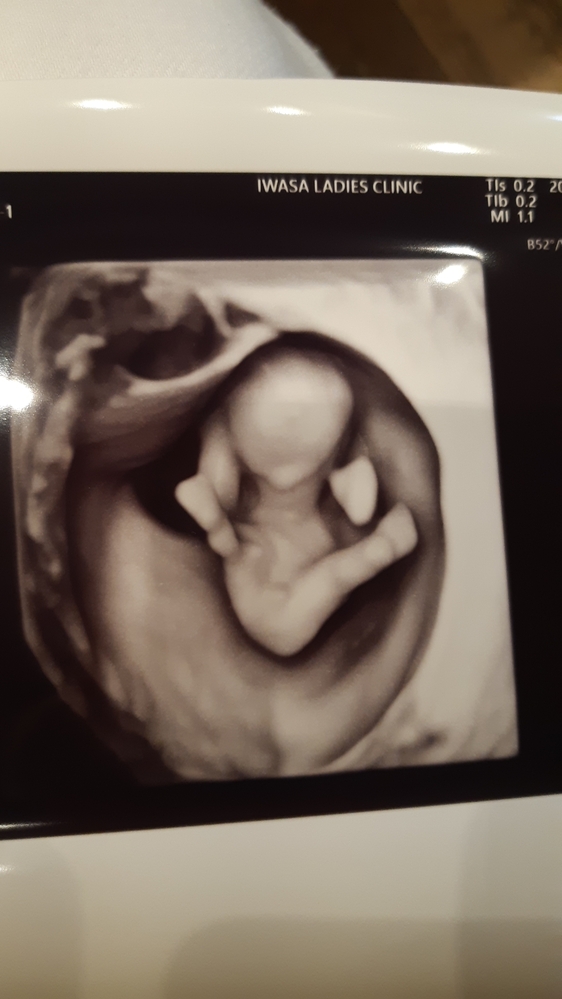

12週2日の4dエコーです 明日で週を迎える妊婦です ま Yahoo 知恵袋

12週2日の画像です しっかり突起物がありますが 初期は女の子も男の子も突 Yahoo 知恵袋

12週6日の妊婦です 今日4dのエコーとってもらったんですが Yahoo 知恵袋

性別について 妊娠12週のエコーです 突起物らしきものが見えますが男の子 Yahoo 知恵袋